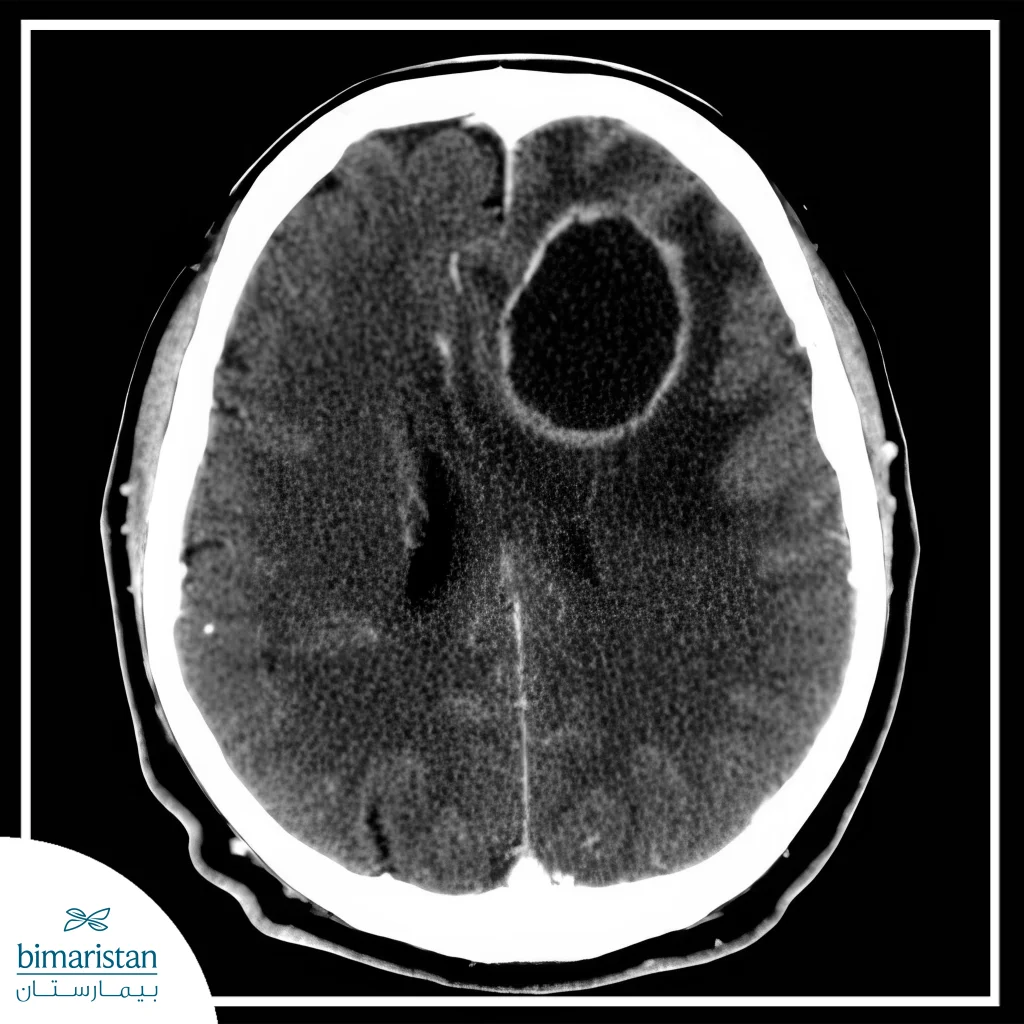

إن خراج الدماغ هو تجمع قيحي داخل أنسجة الدماغ ناتج عن عدوى بكتيرية أو فطرية أو طفيلية، وبالرغم من أنه يُعتبر من الحالات النادرة إلّا أنه حالة طارئة وإسعافية تتطلب التدخل الطبي الفوري لمنع المضاعفات التي قد تكون مهددة للحياة. تحدث هذه الحالة بسبب انتشار العدوى البكتيرية أو الطفيلية من مناطق قريبة من الدماغ كما في حالات التهاب الأذن أو التهاب الجيوب الأنفية، وقد ينتشر من مناطق بعيدة عبر مجرى الدم كما في حالات التهابات الرئة والتهاب الشغاف الجرثومي، وتكون أعراضها هي الحمى والصداع الشديد، والغثيان أو الإقياء، وأعراض عصبية مثل الضعف والتنميل في أحد أطراف الجسم حسب موقع الخراج في الدماغ.

يتخلف حجم خراجات الدماغ حسب نوع العدوى فتتراوح من الصغيرة جداً وحتى الخراجات الكبيرة التي تتجاوز 3 سم، وإن الخراجات الكبيرة تستلزم التدخل الجراحي لتصريفها، حيث أنها تسبب ضغطاً على الدماغ وانزياحاً خطيراً قد يكون مهدداً للحياة، إضافةً إلى ذلك فإن الخراجات القريبة من البطينات تكون علامة إنذار اسعافية تتطلب التدخل الجراحي الطارئ، وذلك بسبب أنها يُمكن أن تتمزق وتسبب التهاب البطين، وهو حالة مميتة حتمية إذا لم تُعالج. قد تكون جراحة إزالة خراج الدماغ في حالات الخراجات المتعددة وخصوصاً إذا كانت كبيرة أو في مناطق حرجة.